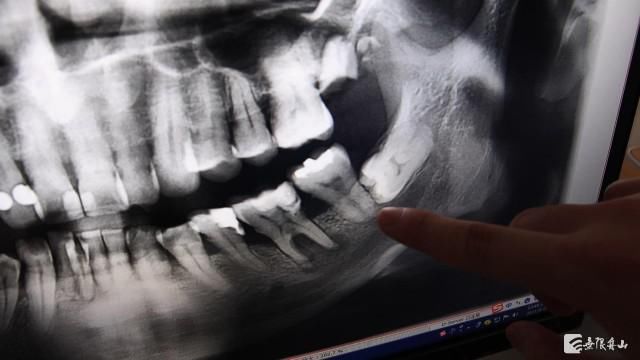

宁波牙科医院舟山分院口腔综合科医师 汪富强:首先我们需要了解一下什么叫智齿?智齿,其实我们用专业的语言称为第三磨牙或者是八号牙,用我们舟山的话说,它叫尽根芽。一般是16到25周岁左右才开始慢慢地萌出,这个时期刚好是我们人类心智成熟的一个时期,所以它也叫智慧牙。它一般会上下左右长4颗,当然就是人类慢慢地进化,现在有些智齿可能不长,或者说长1颗、2颗、3颗这样子。

宁波牙科医院舟山分院口腔综合科医师 汪富强:我们临床上发现很多情况,智齿其实它是需要拔除的。第一个,就是反复发炎对我们生活造成影响,比如说出现红肿、疼痛,这些情况肯定是要拔掉的;第二个的话,就是智齿长的位置有点不对,比如说像斜着长的,歪着长的,可能时间久了以后,四十岁、五十岁左右,慢慢地对我们前面的牙齿会造成非常大的一个不好的影响,就是有些小孩子刚开始在做矫正的时候,我们矫正医生发现这个智齿对我们矫正它也是有影响的,所以会建议把它拔掉;第三个的话,就是后期我们关节会出现一些紊乱或者说疼痛的时候,有可能也会是因为这个智齿的原因,所以这种情况我们也是建议把它拔掉会比较好一些;然后具体还有哪一些智齿可以不用拔呢?比如说智齿位置长得比较对,我们平时刷牙能刷得到,它不容易发炎,这种情况的话一般建议智齿可以考虑把它适当地作为保留。